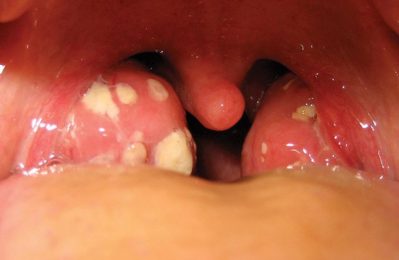

Viêm họng có đốm trắng là một tình trạng không hiếm gặp và gây không ít lo lắng cho bà con. Những đốm trắng xuất...

Khi mắc bệnh viêm họng hạt có mủ, nhiều bà con thường cảm thấy lo lắng về cách điều trị và chăm sóc. Việc này...